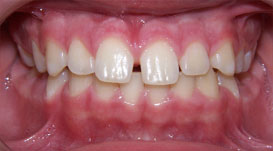

@(轉)門牙縫隙,真的會「漏財」嗎?

幼童門牙缺齒很常見,醫生提醒,8歲後若發現孩子門牙還沒長出來,一定要就醫,把握黃金時間進行前齒矯正。圖/報系資料照 |